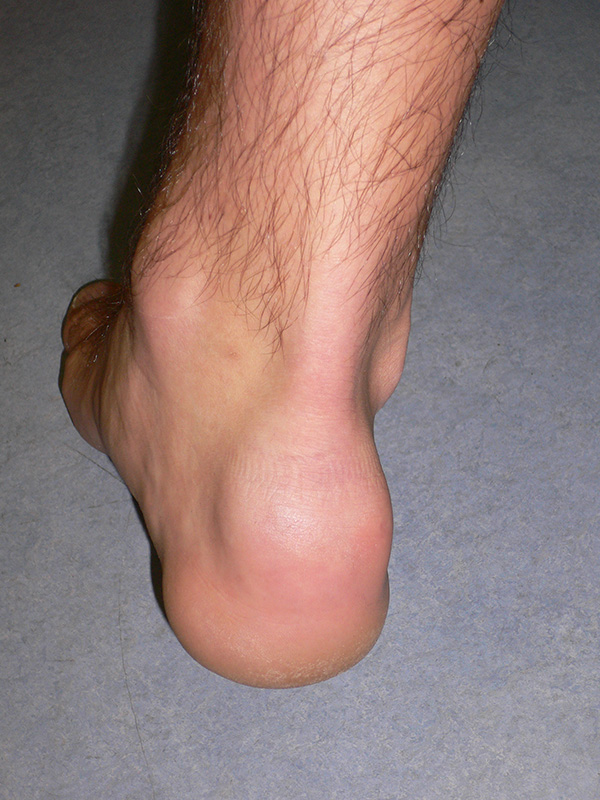

Die Achillessehne wird in Form und Funktion beurteilt. Degenerative Veränderungen der Sehne führen bevorzugt zu einer spindelförmigen Auftreibung der Achillessehne im mittleren Drittel. Eine Abgrenzung zu einer Verdickung des Paratenons, z.B. bei Vorliegen einer Peritendinitis der Achillessehne ist klinisch kaum möglich. Teilweise lassen sich aber knotige Veränderungen des Sehnengleitgewebes tasten.

Abzugrenzen ist hiervon die Insertionstendopathie, die sich durch einen Schmerz am Sehnen-Knochen-Übergang auszeichnet. Etwas kranial davon am posterioren und superioren Kalkaneus finden sich die Beschwerden bei einer Haglundexostose. In vielen Fällen finden sich klinische Mischbilder aus Haglundexostose mit Bursitis subachillea und einer Ansatztendinose der Achillessehne 7.

Abbildung 21: Mid-Portion Tendinopathie der Achillessehne. Die Auftreibung finden sich im mittleren Drittel der Sehne. Es handelt sich um den klassischen Befund bei einer Achillodynie (M. Walther).